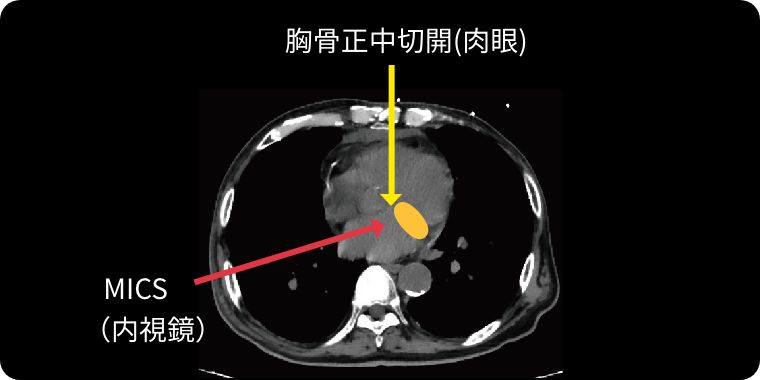

Minimally Invasive Cardiac Surgeryの略で、心臓低侵襲手術のことを意味します。

従来であれば胸骨という胸の真ん中を約20cm程切開しますが、MICSでは肋骨の間を3〜5cm程切開して行います。

当院でのMICS手術では、主に3D内視鏡というカメラと特殊メガネを使用しています。

拡大され立体視となった画面を見ながら、肉眼では確認できない部位まで詳細に把握し手術を行っております。

正中切開では僧帽弁の観察が困難な場合がありますが、内視鏡を用いたMICSでは、奥深くの観察が容易になるため視野の深い僧房弁疾患に対して非常に有用です。肉眼の手術に比べて非常に精度の高い形成術を行う事ができます。また、心房細動の治療や脳梗塞予防の左心耳閉鎖術も同じ傷で一度に行うことが可能です。

当院では可能な方には3D内視鏡を用いた完全内視鏡下手術、及び傷が正面から目立ちにくい脇の下からの方法で、どちらも骨を切らず治療を行なっております。